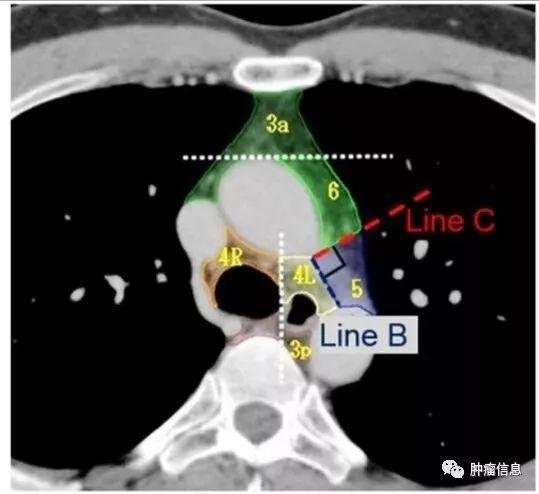

4R:右侧下气管旁,自无名静脉与气管交界区至奇静脉,自气管右侧至气管左侧缘。上界:无名静脉与气管交叉处下缘下界:奇静脉下缘4L:左侧下气管旁,自主动脉弓上缘至左侧主肺动脉上缘,气管左侧缘以左。上界:主动脉弓上缘下界:左肺动脉干上缘气管左侧的矢状面是4L与4R分界线。

主动脉下淋巴结:位于主肺动脉窗肺动脉韧带外侧。上界:主动脉弓下缘下界:左肺动脉干下缘

主动脉旁淋巴结:位于升主动脉,主动脉弓的前面和两侧,迷走神经前面。上界:主动脉弓上缘切线下界:主动脉弓下缘